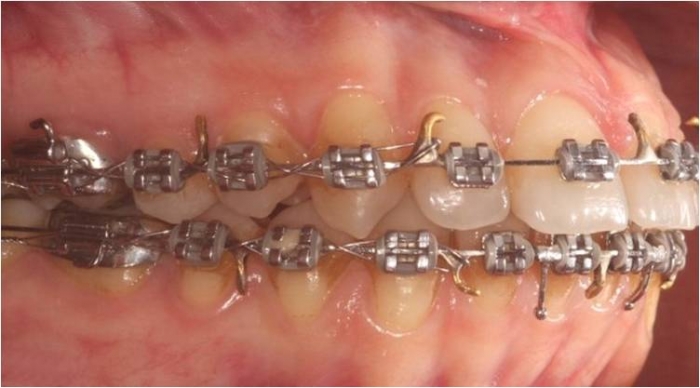

Mordida inicial

Mordida após a cirurgia